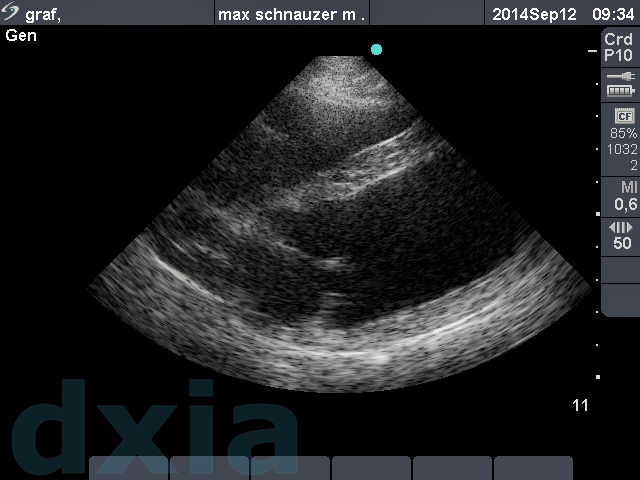

Imágenes obtenidas durante el estudio ecocardiográfico

paraesternal max

Paraesternal derecho eje largo

No se observa dilatación de cámaras cardíacas. Septo IV normal. Válvulas mitrálica y tricuspídea normoimplantadas y sin alteraciones morfológicas.